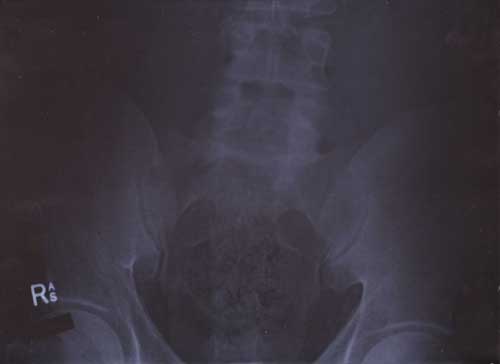

21st January 2000